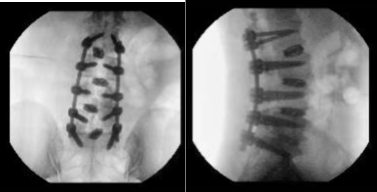

The rods were put onto the pedicle screws and tightened in place with set screws and final tightening with the use of torque lifting screwdriver. Final pictures were taken and found to be in acceptable position.

Neuromonitoring was intact throughout the procedure. Final CT scan was also performed to check the position of cages and the screws and were found to be in acceptable position. After the closure, the patient was extubated and moved to recovery in a stable condition.